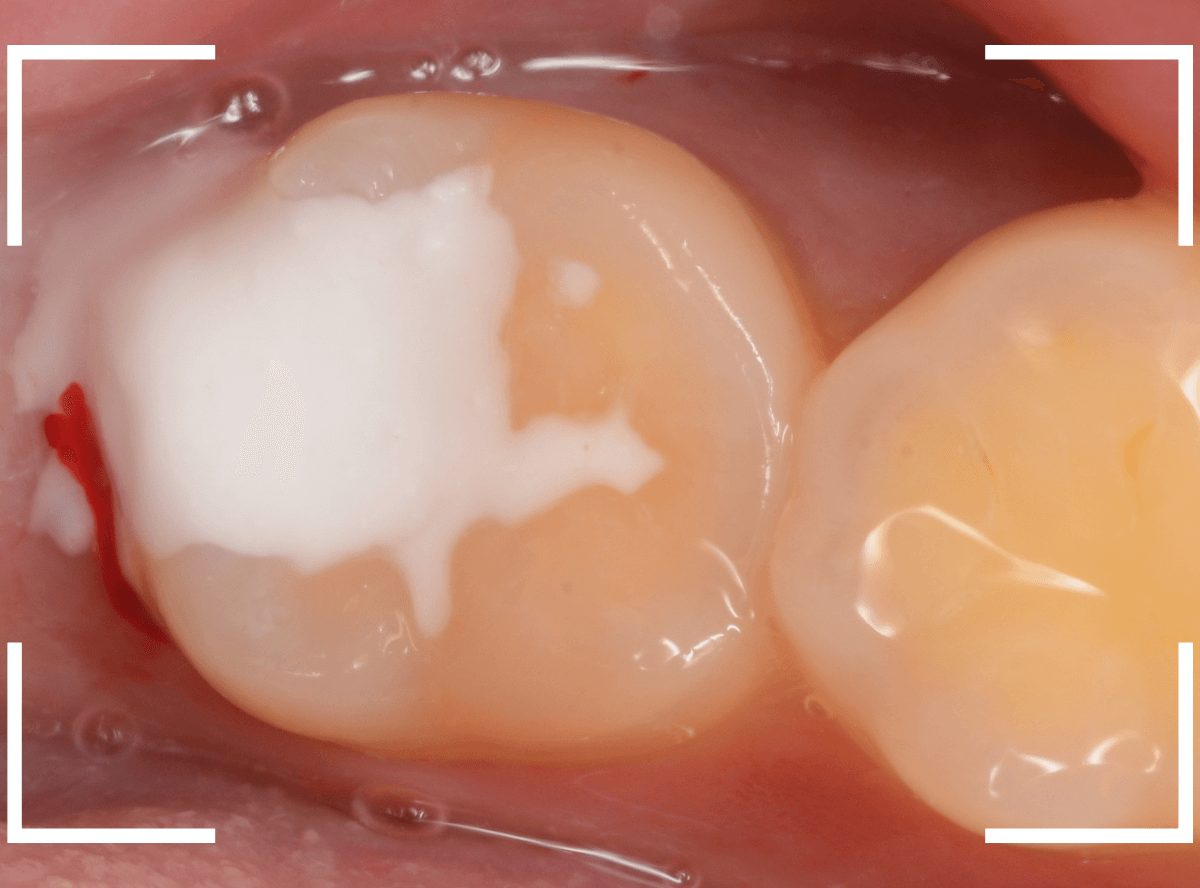

神経を保護するお薬をつめて、セメントで蓋をしてしばらく経過観察します。

経過観察後、痛みがない事が確認できれば、つめものを作製します。